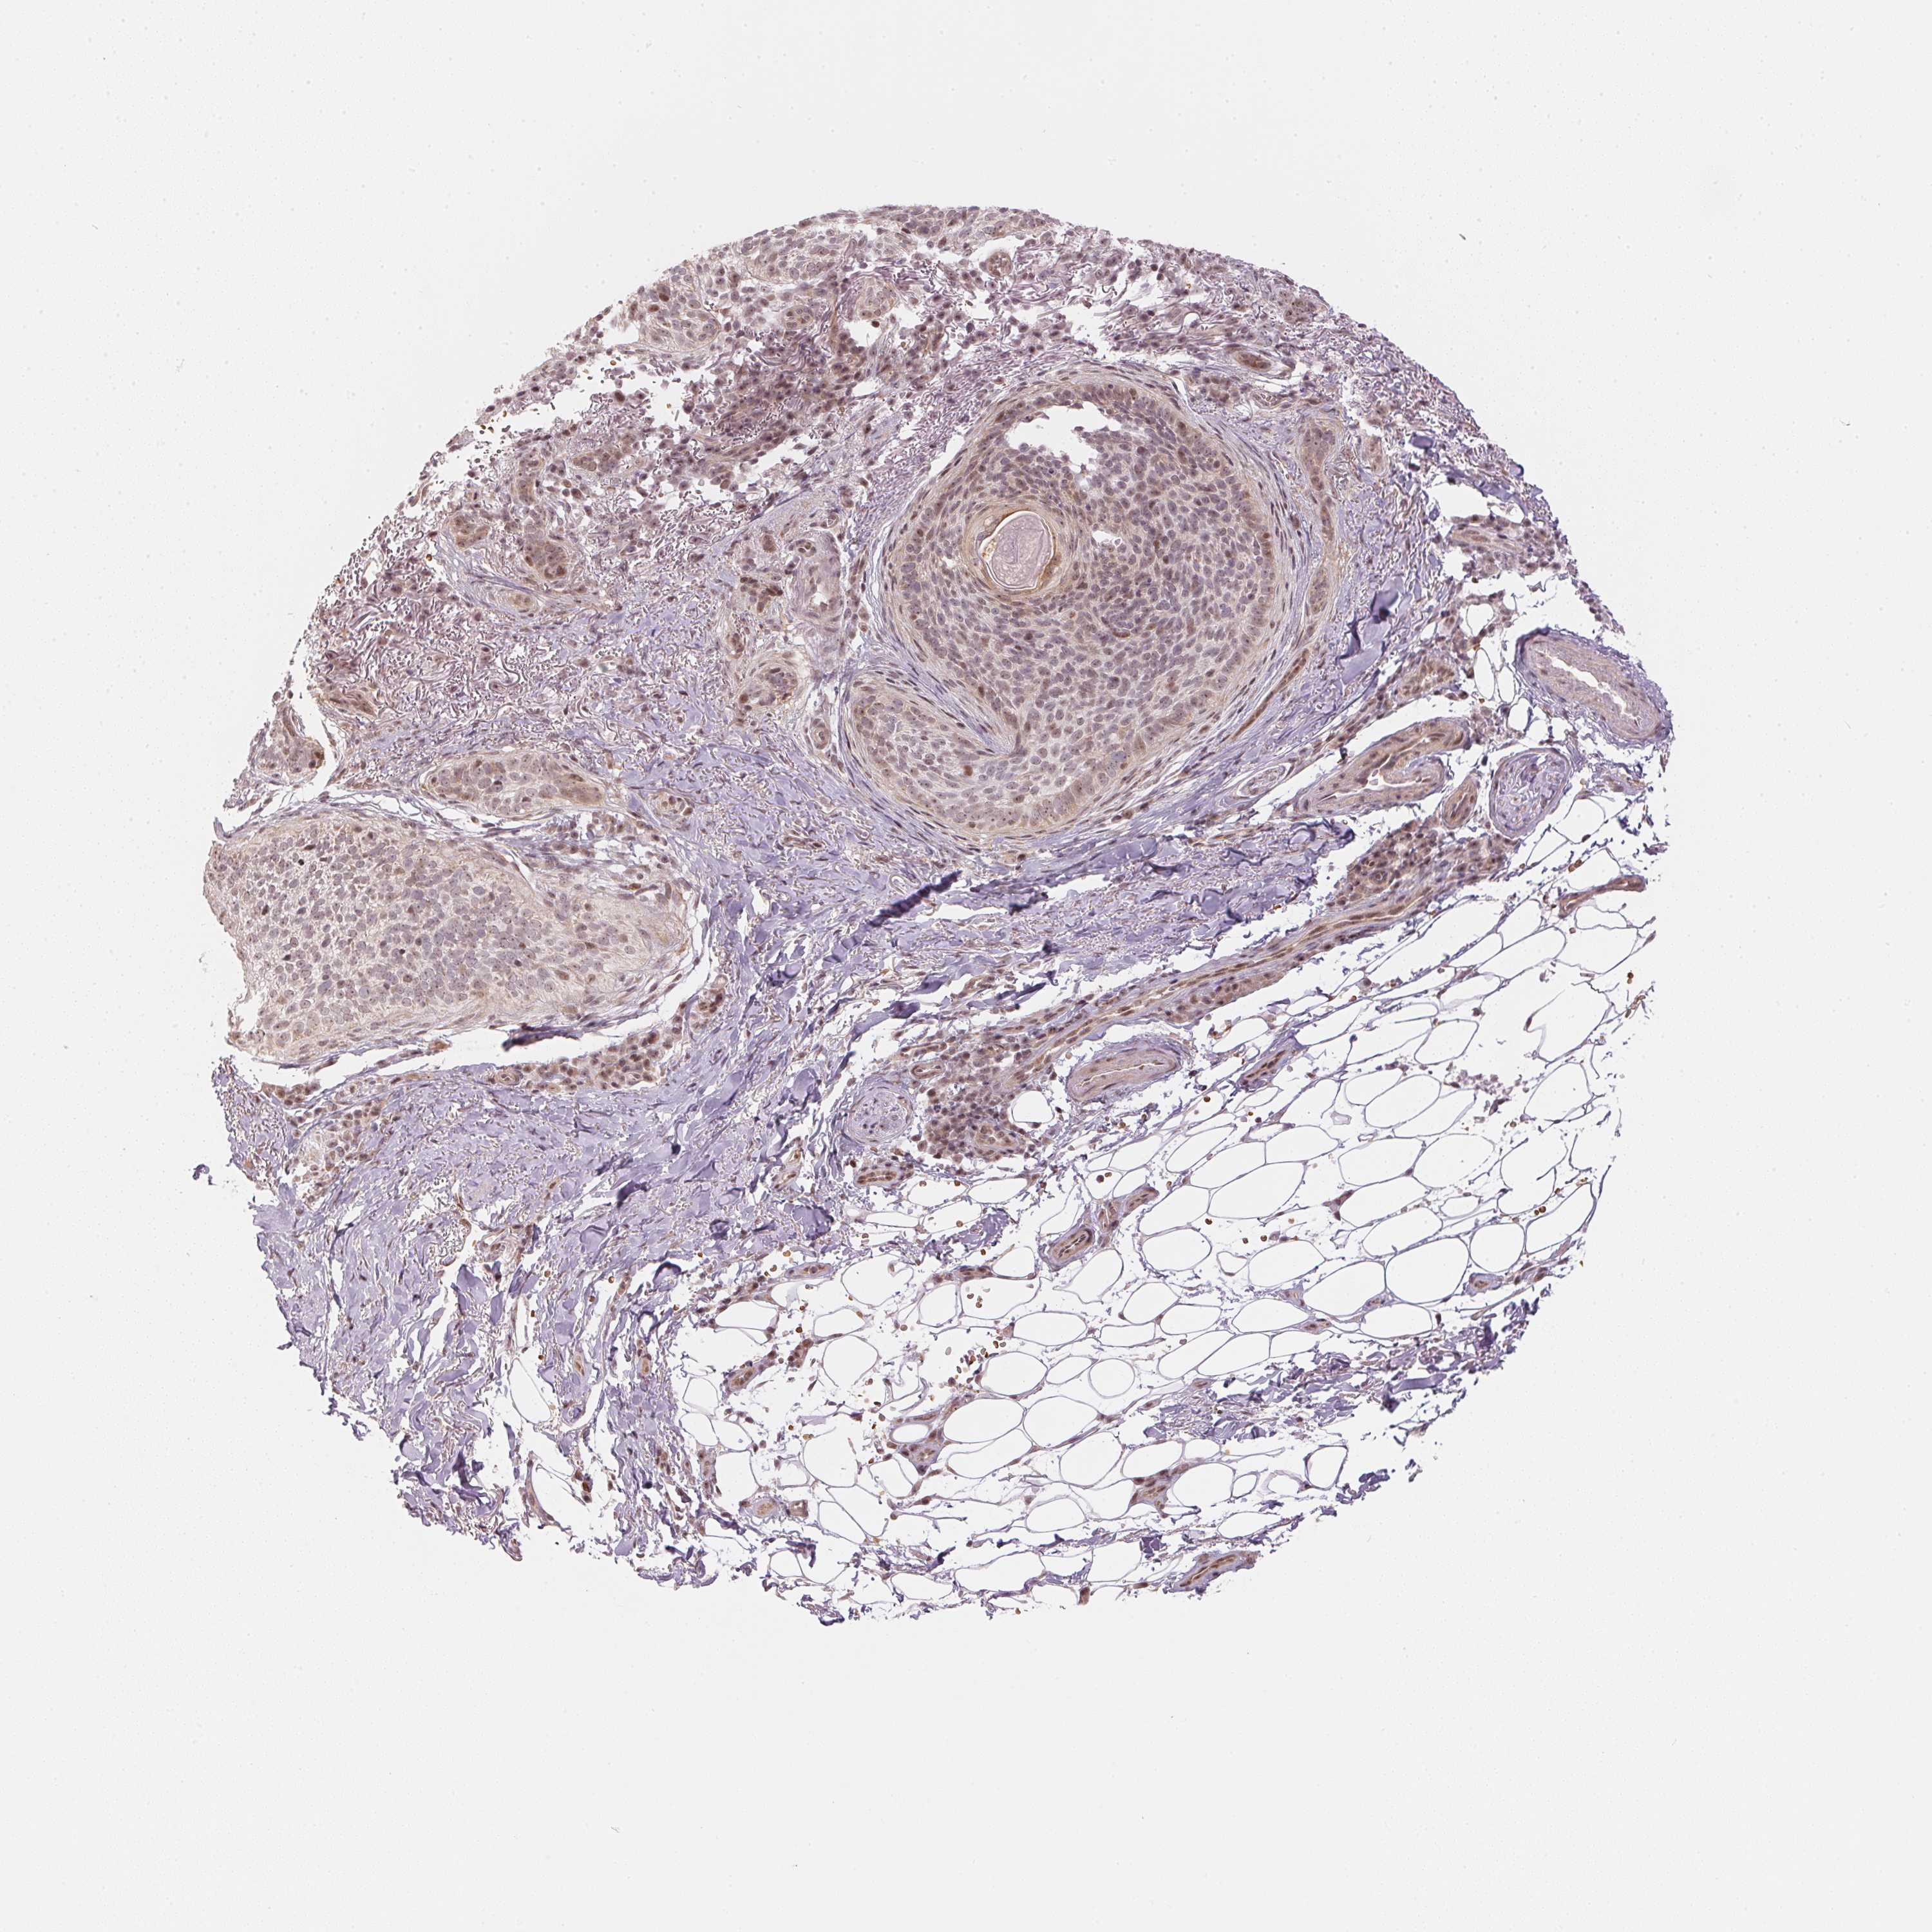

SKIN CANCER - Protein expressioni

A mouse-over function shows sample information and annotation data. Click on an image to view it in a full screen mode. Samples can be filtered based on level of antibody staining by selecting one or several of the following categories: high, medium, low and not detected. The assay and annotation is described here.

Antibody stainingi

Antibody staining in the annotated cell types in the current human tissue is reported as not detected, low, medium, or high, based on conventional immunohistochemistry profiling in selected tissues. This score is based on the combination of the staining intensity and fraction of stained cells.

Each image is clickable and will lead to virtual microscopy that enables deeper exploration of all samples and also displays staining intensity scores, fraction scores and subcellular localization as well as patient and tissue information for each sample.

Antibody HPA065052

Squamous cell carcinoma, NOS